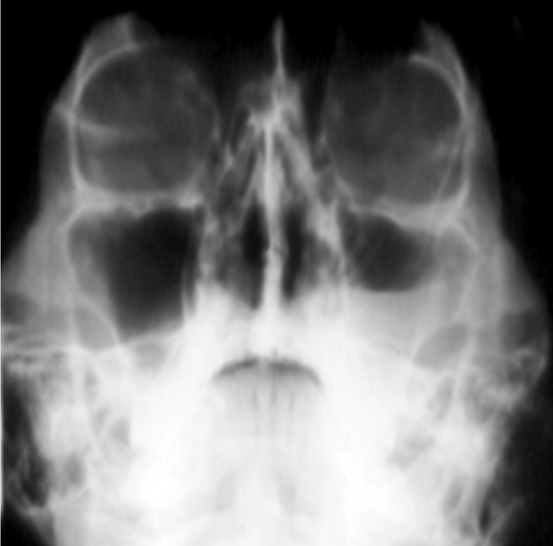

When looking at symmetry and margins, what can you see here?

-superimposition of petrous temporal bone

-cloudy left sinus

-straight upper margin

-defined/cortication??